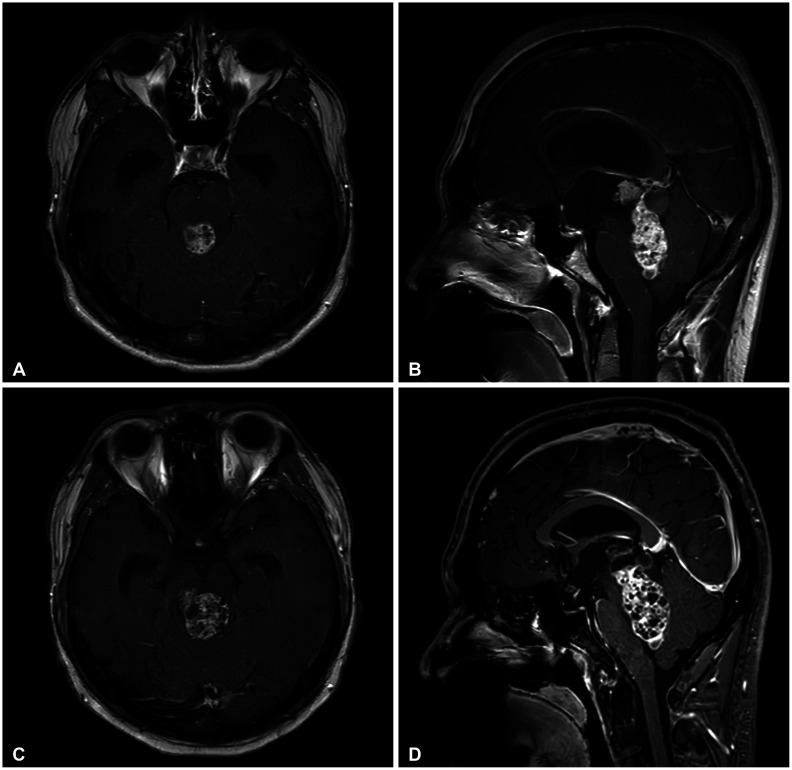

Intracranial growing teratoma syndrome (iGTS) is a rare phenomenon in patients with non-germinomatous germ cell tumor (NGGCT) after chemotherapy or radiotherapy. It manifests as paradoxical growth of teratomatous components, with multiple cystic lesions on cranial imaging despite normalized tumor markers. This paper presents a 22-year-old male with iGTS, diagnosed one month after chemotherapy against NGGCT. Initially diagnosed with presumptive pineal NGGCT causing obstructive hydrocephalus, the patient underwent endoscopic third ventriculostomy and extraventricular drainage with tumor biopsy followed by two chemotherapy cycles. Despite normalization of tumor markers, follow-up MRI showed increased tumor size with honeycomb-like cystic patterns. The patient underwent suboccipital craniotomy for tumor removal via combined telovelar and infratentorial supracerebellar approaches. The final pathology confirmed mature teratoma. However, postoperative bleeding and left thalamic infarction occurred, resulting in severe neurological deficits. Despite challenges, the patient eventually regained the ability to follow simple commands. To understand iGTS pathophysiology, several hypotheses, including the differentiation of immature components and the uninhibited growth of mature components induced by chemotherapy or radiotherapy, were explored. Surgical intervention remains as an ideal treatment, while clinical trials investigate chemotherapy options. Frequent imaging follow-ups are crucial for early detection in iGTS for NGGCT patients.